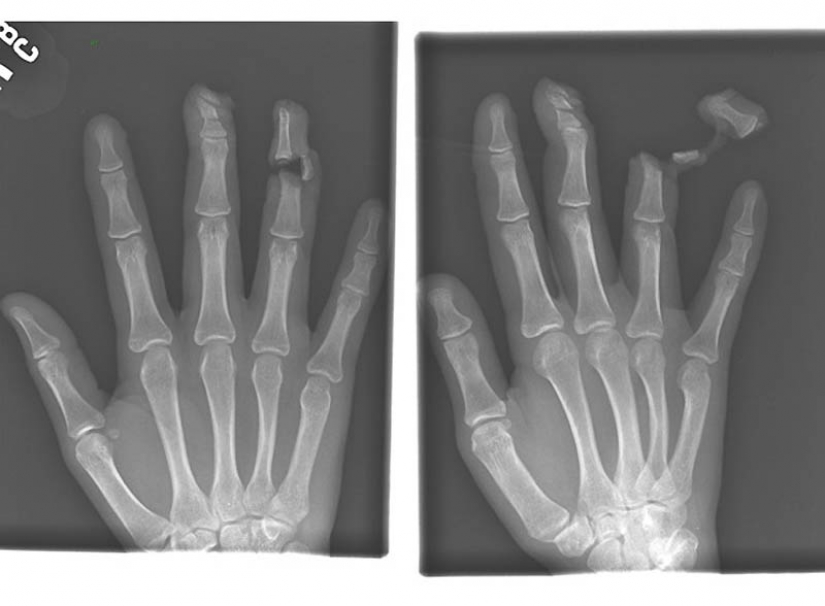

4. El clavo en los huesos de los dedos índice y medio de hombres adultos.